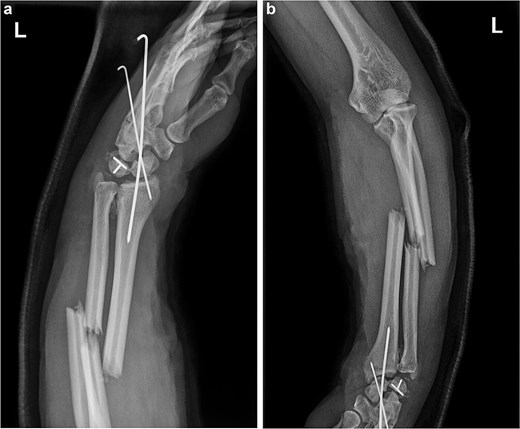

(a and b) After the first operation, X-ray images revealed that the volar displaced scaphoid fracture end had been incorrectly fixed to triquetrum fracture end. Temporary fixation of the unstable wrist joint was achieved using Kirschner wires, while the ulna and radius were not fixed. The lunate bone had not yet been completely repositioned.